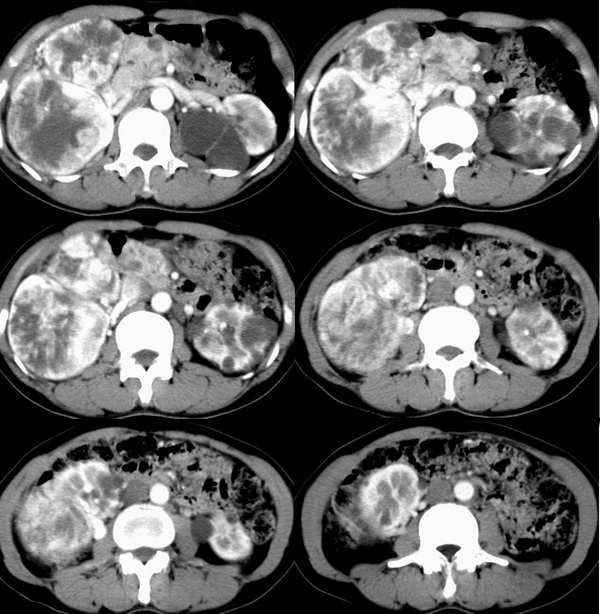

静脉期

右肾体积增大,形态失常,其内可见多发低密度影,增强后动脉期病灶实质明显强化,低密度区未见强化,静脉期病灶呈等密度,考虑右肾癌,左肾多发囊肿,多囊胰

右肾体积增大,形态失常,其内可见多发低密度影,增强后动脉期病灶实质明显强化,低密度区未见强化,静脉期病灶呈等密度.

考虑1右肾囊性癌,2左肾多发囊肿,3多囊胰可能?